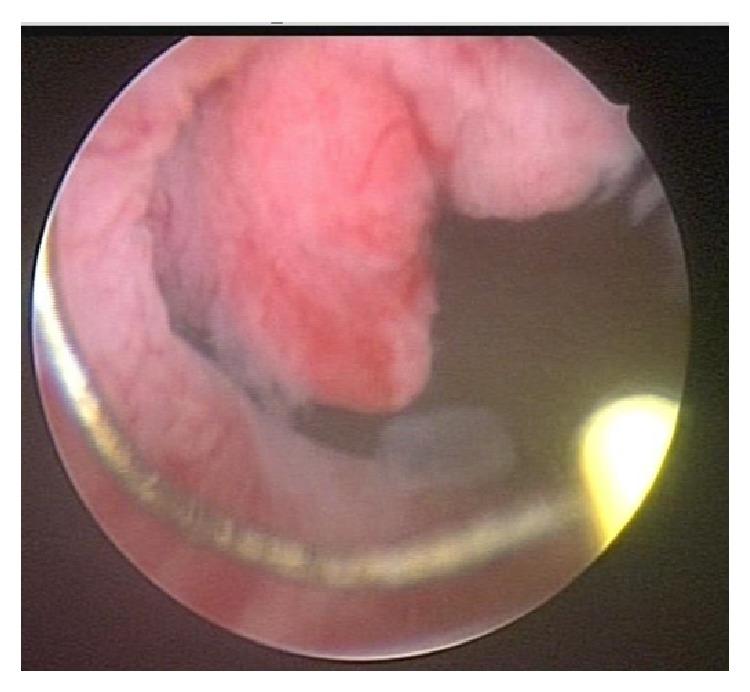

Primary mucinous adenocarcinoma is an extremely rare type of bladder cancer, with aggressive behavior and poor response to chemotherapy and radiotherapy. The symptoms are similar to those of other bladder tumors. Surgery is the main treatment and remains the only curative option. There may be a progression from mucinous metaplasia to mucinous adenoma and then mucinous adenocarcinoma. We present the case of a 40-year-old woman with recurrent lower urinary tract infections, submitted to imaging tests, which showed a bladder tumor. After transurethral resection, pathology showed intestinal mucinous carcinoma. Metastatic work-up was negative. New surgical procedure showed metaplasia but no recurrence of the carcinoma. The patient is now using antibiotic prophylaxis and will undergo a cystoscopy every 3 months and computed tomography in one year.

原发性黏液腺癌是一种极为罕见的膀胱癌类型,具有侵袭性,对化疗和放疗反应不佳。其症状与其他膀胱肿瘤相似。手术是主要治疗方法,也是唯一的治愈选择。可能存在从黏液化生发展为黏液腺瘤,进而发展为黏液腺癌的过程。我们报告一例40岁女性,反复出现下尿路感染,接受影像学检查显示膀胱肿瘤。经尿道切除术后,病理显示为肠道黏液癌。转移评估为阴性。再次手术显示为化生,但癌未复发。患者目前正在进行抗生素预防,每3个月将接受一次膀胱镜检查,一年后进行计算机断层扫描。